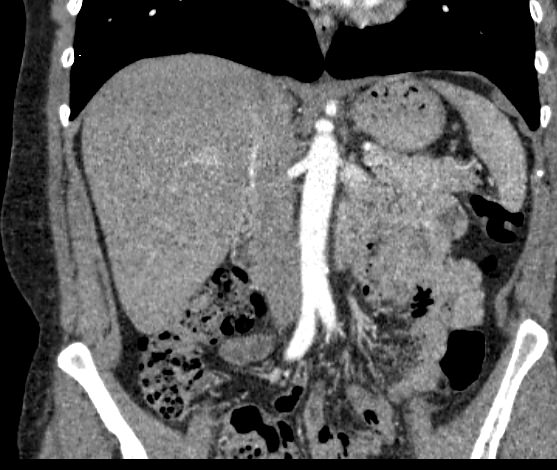

Мультиспиральная компьютерная томография (МСКТ) брюшной полости и забрюшинного пространства относится к современным лучевым методам исследования, с помощью которого можно оценить состояние органов брюшной полости (печени, желчного пузыря, поджелудочной железы, селезенки), забрюшинного пространства с расположенными в нем почками, надпочечниками, мочеточниками и прилегающих к ним кровеносных сосудов и лимфатических узлов.

С помощью мультиспиральной компьютерной томографии проводятся послойные рентгеновские снимки исследуемой области с толщиной среза от 0,5 мм. Затем полученные данные преобразуются в цифровые трехмерные модели органов и систем в мельчайших подробностях.

При подозрении на опухоли, воспалительные процессы, гнойные очаги назначается КТ брюшной полости и забрюшинного пространства с внутривенным болюсным контрастированием. Для этого пациенту внутривенно вводится рентгеноконтрастное вещество на основе йода. Благодаря усиленному кровоснабжению, которое обычно наблюдается в патологических очагах, препарат накапливается в структуре патологических образований и помогает врачу-рентгенологу выявить изменения внутренних органов.

Метод контрастирования помогает максимально точно выявить очаг патологии уже на начальной стадии, а также установить его локализацию, точные размеры, форму и особенности кровоснабжения. Возможности мультиспиральной компьютерной томографии позволяют выполнить своевременную диагностику заболеваний внутренних органов, от чего напрямую зависит эффективность лечения.